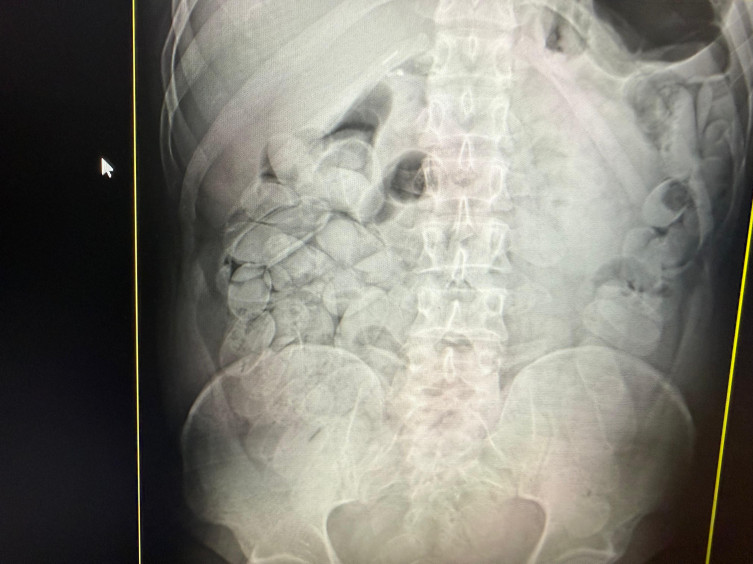

Diante da suspeita de ingestão de cápsulas, os passageiros foram encaminhados ao Pronto-Socorro de Corumbá, onde exames de raio-x confirmaram que as 17 pessoas haviam ingerido cápsulas de droga.

Divulgação/Receita Federal

Exames de raio-x comprovaram a ingestão de entorpecente por 17 pessoasNo total, 18 bolivianos foram detidos, resultando na apreensão de aproximadamente 20 quilos de pasta base de cocaína, causando um prejuízo estimado em cerca de R$ 1 milhão ao crime organizado, segundo a Receita Federal.